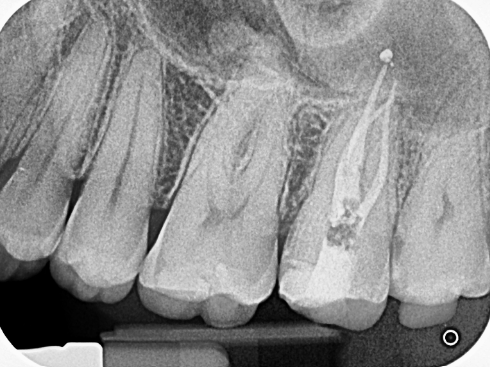

La endodoncia es la solución para conservar dientes que han sido afectados por caries profundas o trauma, eliminando el tejido dañado y protegiendo la estructura dental.

En AIEN, realizamos endodoncias utilizando lo último en tecnología radiográfica y tomografía, asegurando tratamientos eficientes y precisos que mantienen tus dientes funcionales y sin dolor